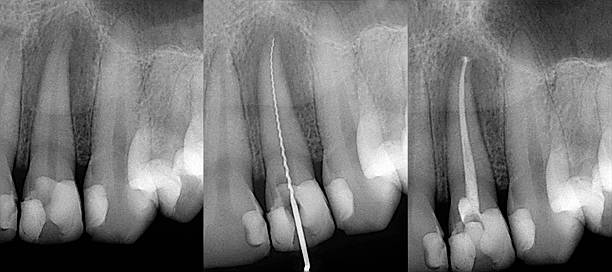

Vår rotfyllningsbehandling räddar dina tänder från förlust och lindrar

smärta orsakad av djupa kariesinfektioner eller skador. Med skickliga tandläkare och avancerad teknik

utförs proceduren noggrant och smärtfritt. Återfå en frisk och smärtfri munhälsa med vår

rotfyllningsbehandling.